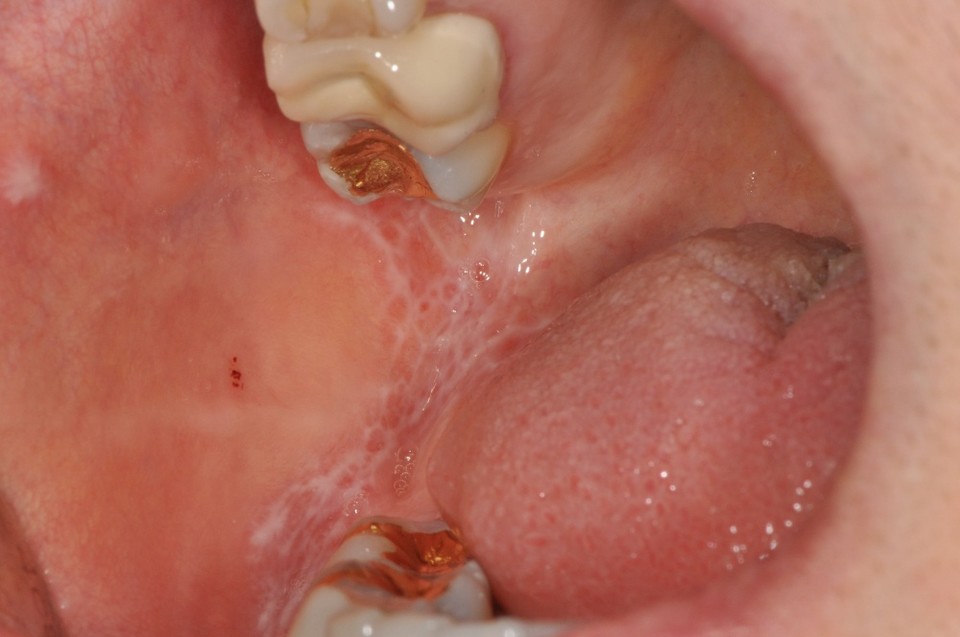

간혹 구강점막에 레이스 형태의 흰색 선이 생기거나 주변으로 빨간 발적이나 궤양을 동반하는 편평태선이 발생하기도 한다.

편평태선의 경우 진성편평태선과 복용하는 약이나 음식과 관련된 태선양 반응으로 나뉘는데, 특정약물에 의해 발생하는 경우 내과의와 상의하여 약의 종류를 변경하거나 알러지를 일으키는 원인을 찾아 제거하는 것이 권장된다.

편평태선도 스테로이드의 성분을 도포하거나 복용하여 치료하게 된다. 스테로이드를 장기간 복용하는 경우 혈당을 높이거나 면역저하 등 전신건강에 영향을 줄 수 있고 국소적으로 오래 사용시 칸디다 같은 진균 감염이 있을 수 있어 1~2주정도 사용 후 중단하였다가 병증에 따라 다시 사용하는 것을 추천한다.